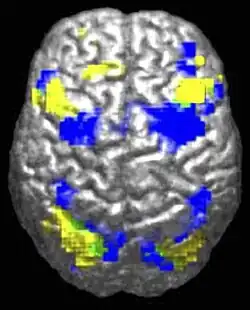

The beginnings of empathy lie in the brain. When a person empathises with another person, their brain triggers neurons that match the neurons in the brain of the person in distress. Or quite simply, just by perceiving an emotion in someone the neuron mechanisms that are responsible for that emotion in our brains are switched on. This phenomenon was first discovered from studies on rhesus monkeys, in which a class of neurons called mirror neurons were found in the ventral premotor and posterior parietal cortices in the brain. (Rizzolatti, Fogassi & Gallese, 2001 cited in Decety & Meyer, 2008). The evidence for mirror neurons in humans is a little less solid, however studies using functional magnetic resonance imaging (fMRI) have found similar results involving pain - when a person perceives someone in pain, the neural circuits for pain in the observer are activated, as if they too are experiencing pain (Decety & Meyer, 2008; Mikulincer & Shaver, 2010).

Empathy theorist Jean Decety also proposes that the experience of empathy likely involves other parts of the brain, such as the frontopariental and prefrontal circuits, as the person empathising must be able to differentiate himself or herself from the person in distress. In addition, executive functions instantiated in the prefrontal cortex may play a part, as this part of the brain helps to regulate emotions and yield mental flexibility (Decety & Meyer, 2008).

Empathy is visible in the brain, and likely involves ‘mirror neurons’ which help to replicate the emotion we perceive in our own brains. Empathy begins in children when they are born and gradually develops and matures throughout our lives.